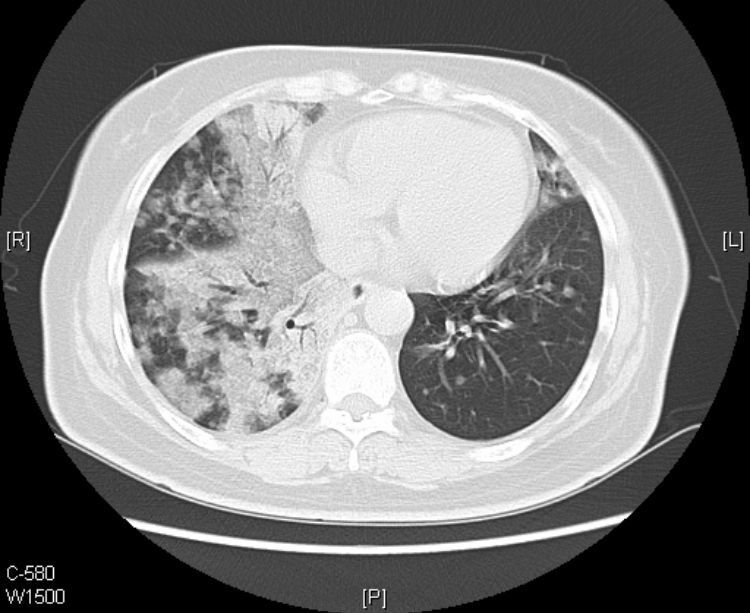

在影像上,黏液腺癌分两种类型:结节肿块型和肺炎型。

肺炎型的初期常被误诊为肺炎,上图的老太太就属于这个类型。

接着看她往下的CT层面:

从CT片上我们可以看到:老人的黏液腺癌还发生了气道转移。

CT提示气道播散的征象包括:多发小叶中心结节,分支模糊呈树芽征,通常边界不清,可见磨玻璃影。

1.气道播散形成的结节呈聚集分布,可以融合增大,有时也可形成空腔。